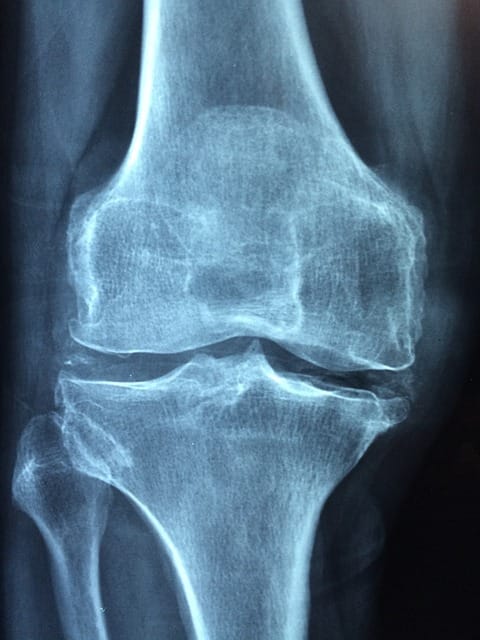

Arthritis affects more than 54 million people in the US. But did you know there are options you have to self-treat before considering surgery?

Arthritis: “My doctor says I’m ‘Bone-On-Bone'” What should you do? Read More »